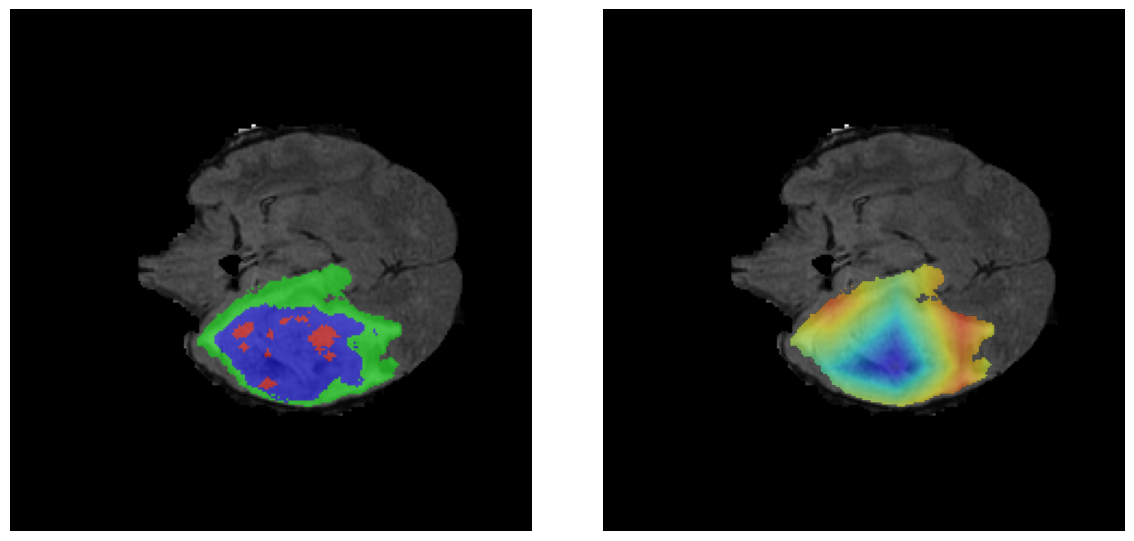

Ejemplos HGG - Atención en Núcleo Necrótico y Tumor Realzado

HGG Grad-CAM++ 1 HGG Grad-CAM++ 2 HGG Grad-CAM++ 3 HGG Grad-CAM++ 4 HGG Grad-CAM++ 5 HGG Grad-CAM++ 6

Los heatmaps muestran que el modelo concentra su atención en las regiones de Tumor Realzado (rojo) y Núcleo Necrótico (azul), características patológicas clave de los gliomas de alto grado.